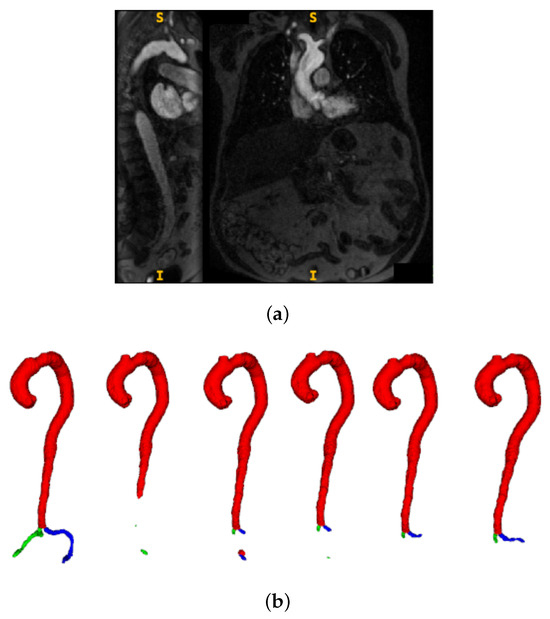

Transcatheter aortic valve implantation (TAVI) is a minimally invasive procedure for treating severe aortic stenosis, where optimal vascular access route selection is critical to reduce complications. It requires careful selection of the iliac artery with the most favourable anatomy, specifically, one with the [...] Read more.

Transcatheter aortic valve implantation (TAVI) is a minimally invasive procedure for treating severe aortic stenosis, where optimal vascular access route selection is critical to reduce complications. It requires careful selection of the iliac artery with the most favourable anatomy, specifically, one with the largest diameters and no segments narrower than 5 mm. This process is time-consuming when carried out manually. We present an active learning-based segmentation framework for contrast-enhanced Cardiac Magnetic Resonance (CMR) data, guided by probabilistic uncertainty and pseudo-labelling, enabling efficient segmentation with minimal manual annotation. The segmentations are then fed into an automated pipeline for diameter quantification, achieving a Dice score of 0.912 and a mean absolute percentage error (MAPE) of 4.92%. An ablation study using pre- and post-contrast CMR showed superior performance with post-contrast data only. Overall, the pipeline provides accurate segmentation and detailed diameter profiles of the aorto-iliac route, helping the assessment of the access route. Full article

Show Figures